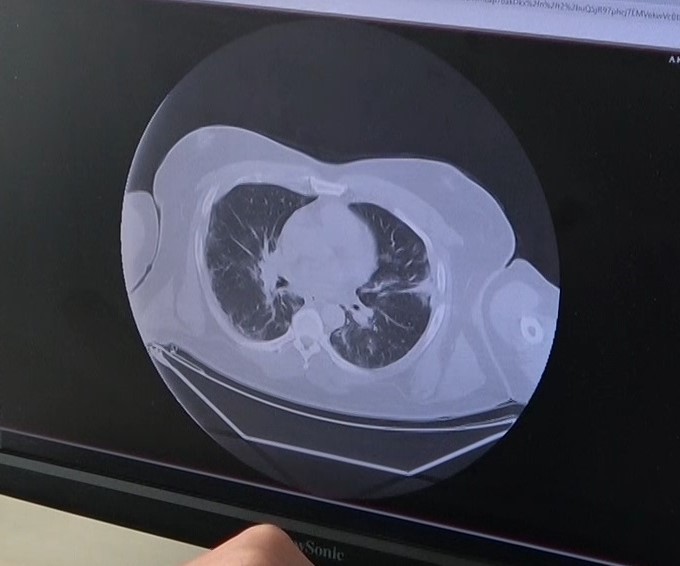

Koronavirüsün bulaşmasından sonra 3 gün içinde hızla akciğere nasıl yayıldığını gösteren grafikleri gösteren Dr. Demir, hastanede yoğun bakımda yatış yapanların çoğunluğunun delta varyantı olduğunu söyledi.